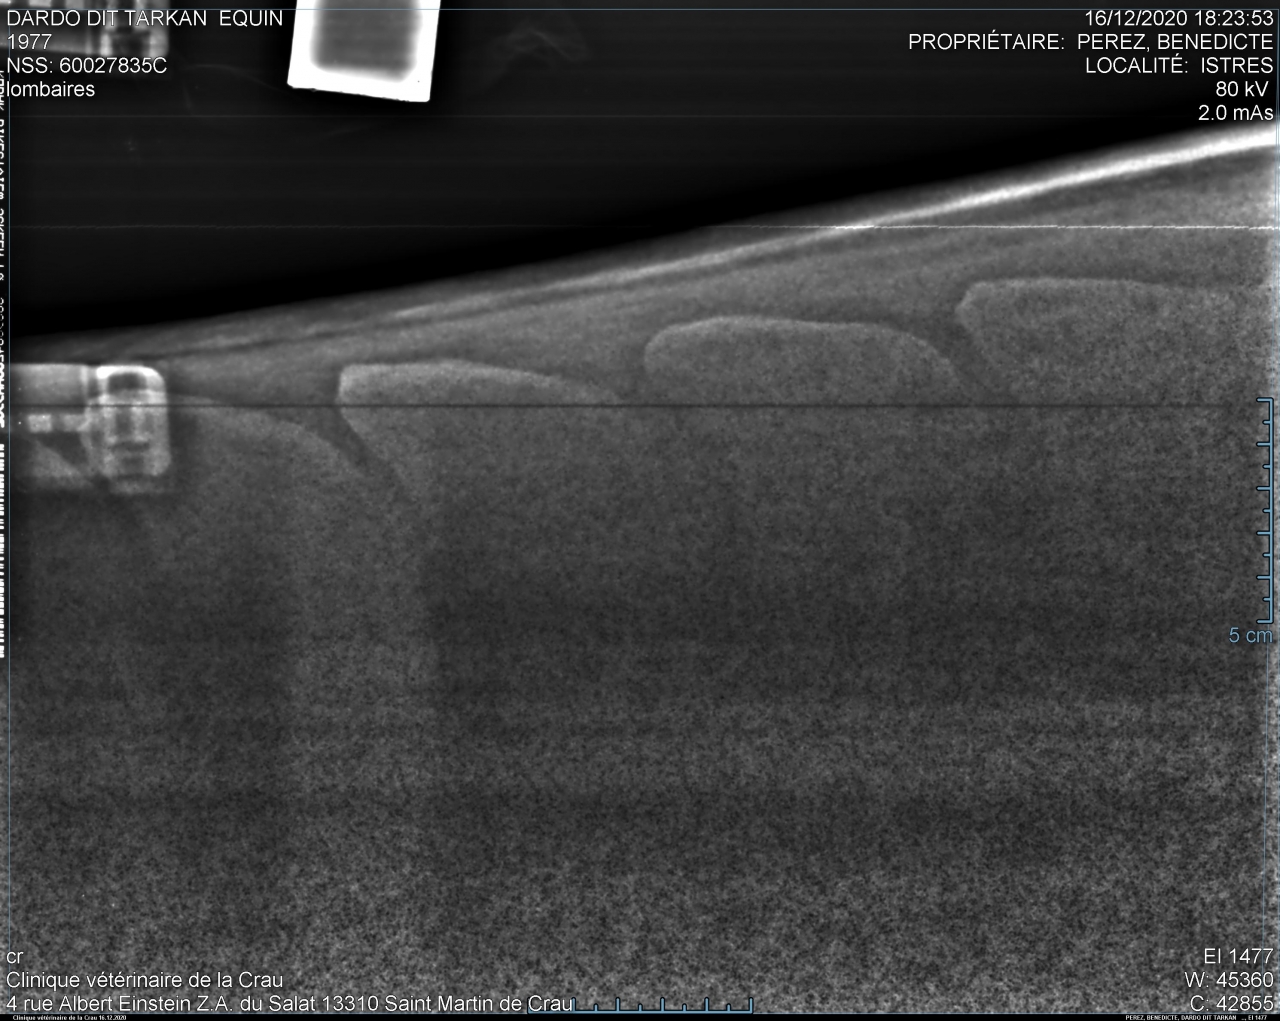

| Dire merci | bon... sans suspens aucun voilà les radios de Takhan : garrot très bien : ![]() ![]() T15/16 : la cata ![]() ![]() puis les lombaires.... acceptable mais pas génial : ![]() ![]() Je le savais mais ça fait un choc tout de meme... Je débriefe avec la véto aujourd'hui pour savoir ce qu'on fait, méso, laser? bref on va voir... Il est très très contracturé sur le dos donc déjà on va traiter ça avec mon osteo qui est aussi shiatsu girl et masseuse. Ça fait chier quand meme... |

| Dire merci | Alors oui dawa , sur les radios du garrot, tu vois que les vertèbres sont bien écartées, l'os parait visuellement "propre". Tout va bien. Sur les lombaires c'est un gros plan sur le haut des vertèbres et tu vois que l'espacement entre les vertèbres est mince mais existant. Rien ne se touche. On considère que c'est problématique quand l'espacement est en dessous de 4mm. Pour le dos, donc T15/T16 (sous mes fesses pour faire simple), tu vois que les vertèbres se touchent, et en plus, sur un coté de la radio tu vois une petite tache blanche entre les 2 vertèbres c'est ce qu'on appelle le chevauchement. Y pas encore de pont osseux donc on peut pas dire qu'il soit soudé encore.Pas complètement quoi. |